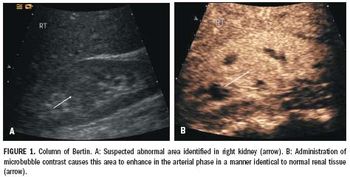

Ultrasound is often the preliminary investigation for many diseases affecting the kidney.

Ultrasound is the most commonly used abdominal imaging modality. The addition of color and spectral Doppler imaging has been particularly beneficial. When ultrasound findings are nonspecific, however, patients are generally referred to CT or MRI